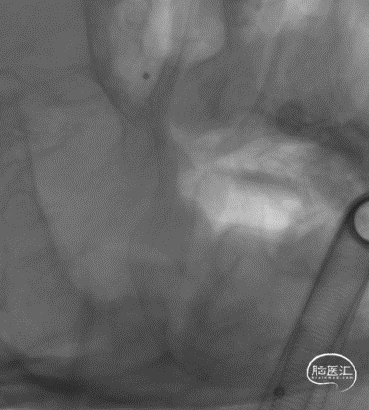

J-Tube™血流导向密网支架释放后处理狭窄。

Gateway 3.5*15 球囊到位

充盈球囊

球囊后处理效果。

处理前

处理后